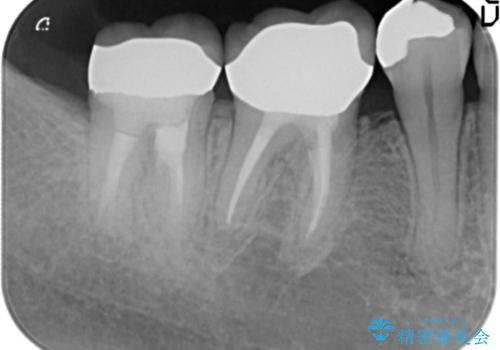

右上小臼歯(右上5)はオールセラミッククラウン(e-max press)、下顎臼歯(下顎両側67)はメタルボンドクラウンによりやりかえることにしました。

再根管治療はご希望されず、行っておりません。